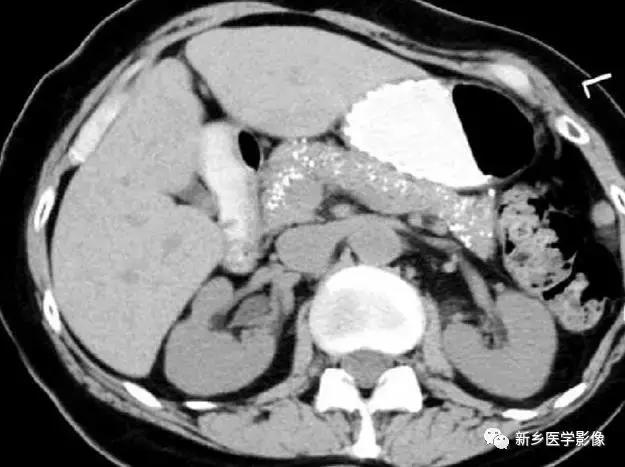

慢性胰腺炎

主要表现为胰腺体积缩小,钙化,有时候假性囊肿囊壁也可钙化。